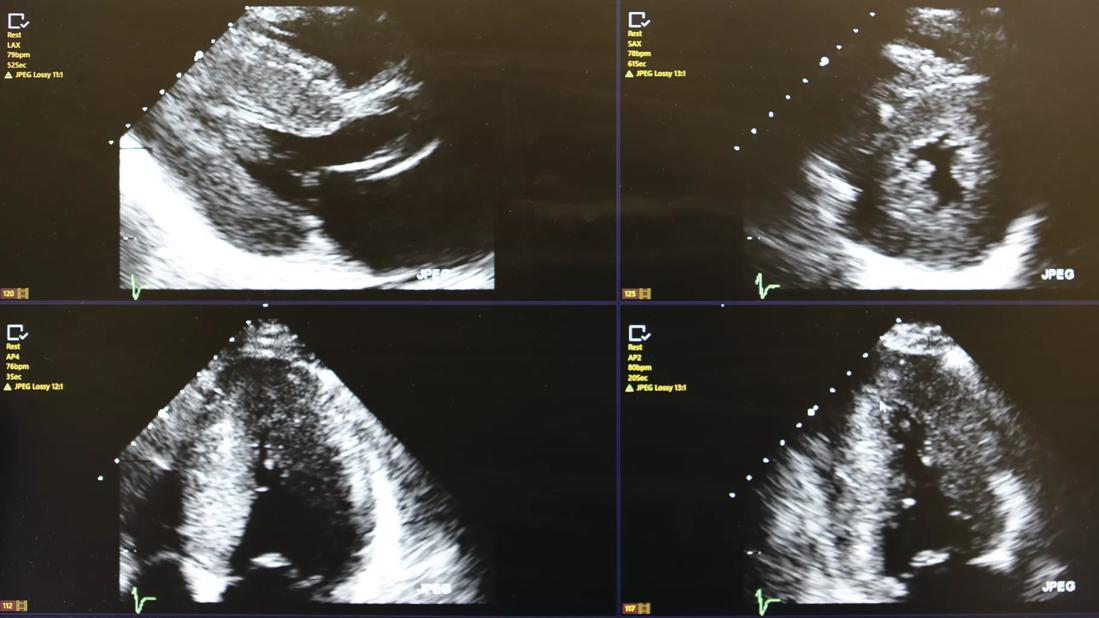

Cleveland Clinic Florida has developed a comprehensive noninvasive imaging protocol for amyloidosis evaluation. Echocardiography is an ideal screening test, demonstrating not only left ventricular hypertrophy but also typical abnormalities of the atria and valves. Most important is the performance of strain imaging as part of the standard echo protocol. This characterizes myocardial dynamics and, in amyloidosis, a characteristic pattern of “apical-sparing” can be noted. Cardiac MRI is also a useful tool as characteristic patterns of late gadolinium enhancement and the presence of increased extracellular volume may be seen.

Echocardiogram demonstrating left ventricular hypertrophy and typical bright speckled appearance. Though very suggestive of ATTR cardiac amyloidosis, it is not sufficient. Only myocardial biopsy or positive pyrophosphate scan may confirm the diagnosis.